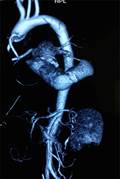

Kết quả siêu âm tim qua thành ngực cho thấy hình ảnh sùi van động mạch chủ, áp xe thành trước động mạch chủ lan tới 1/3 trên vách liên thất gây hở chủ nhiều. Sùi van hai lá gây hở hai lá nhiều và giãn các buồng tim (Hình 1,2). Điện tim đồ cho thấy block nhĩ thất cấp 3 (Hình 3). Cấy máu cấp ở 3 vị trí khác nhau cho kết quả âm tính. Bệnh nhân được hội chẩn nội – ngoại khoa và được chỉ định phẫu thuật cấp cứu.

| Hình 1,2: Hình ảnh abscess gốc ĐMC và vách liên thất trên siêu âm tim. | |